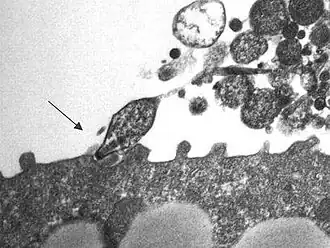

Mycoplasma pneumoniae is een bacteriesoort. Dit micro-organisme onderscheidt zich van soorten uit andere bacteriegeslachten door het ontbreken van een celwand en is slechts omgeven door een dun celmembraan dat rijk is aan sterolen. Het is een van de kleinste bacteriën die er bestaan.